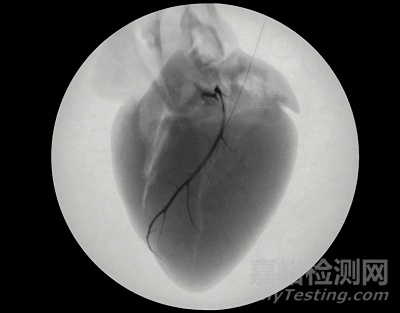

一些復雜的心律失常通過將電極導線放入心臟靜脈來治療,這通常是進入心臟左側(cè)靜脈是最安全方法。然而,與這些靜脈相比,電極導線尺寸相對較大,很難進入。因此,導線僅能放置在心臟外表面附近最大的心臟靜脈中。

因此需要一種新型的電極導線來實現(xiàn)捕獲更多的心肌細胞,要實現(xiàn)這個目標就需要將電極插入到更深的心臟靜脈中。很可惜以目前上市的電極導線很難實現(xiàn)進入更深心臟靜脈。

為此Rhythio Medical開發(fā)一款顛覆性的電極導線---Liquid Wire,能夠像水一樣被注入到心臟靜脈中,進入到心臟靜脈深處。

Liquid Wire植入過程也非常簡單,只需通過一個專有的輸送系統(tǒng)將兩種液體化合物同時注入到患者的心臟靜脈中。在心臟靜脈中兩種化合物反應固化,形成一帶深入到心臟靜脈深處的導電水凝膠。